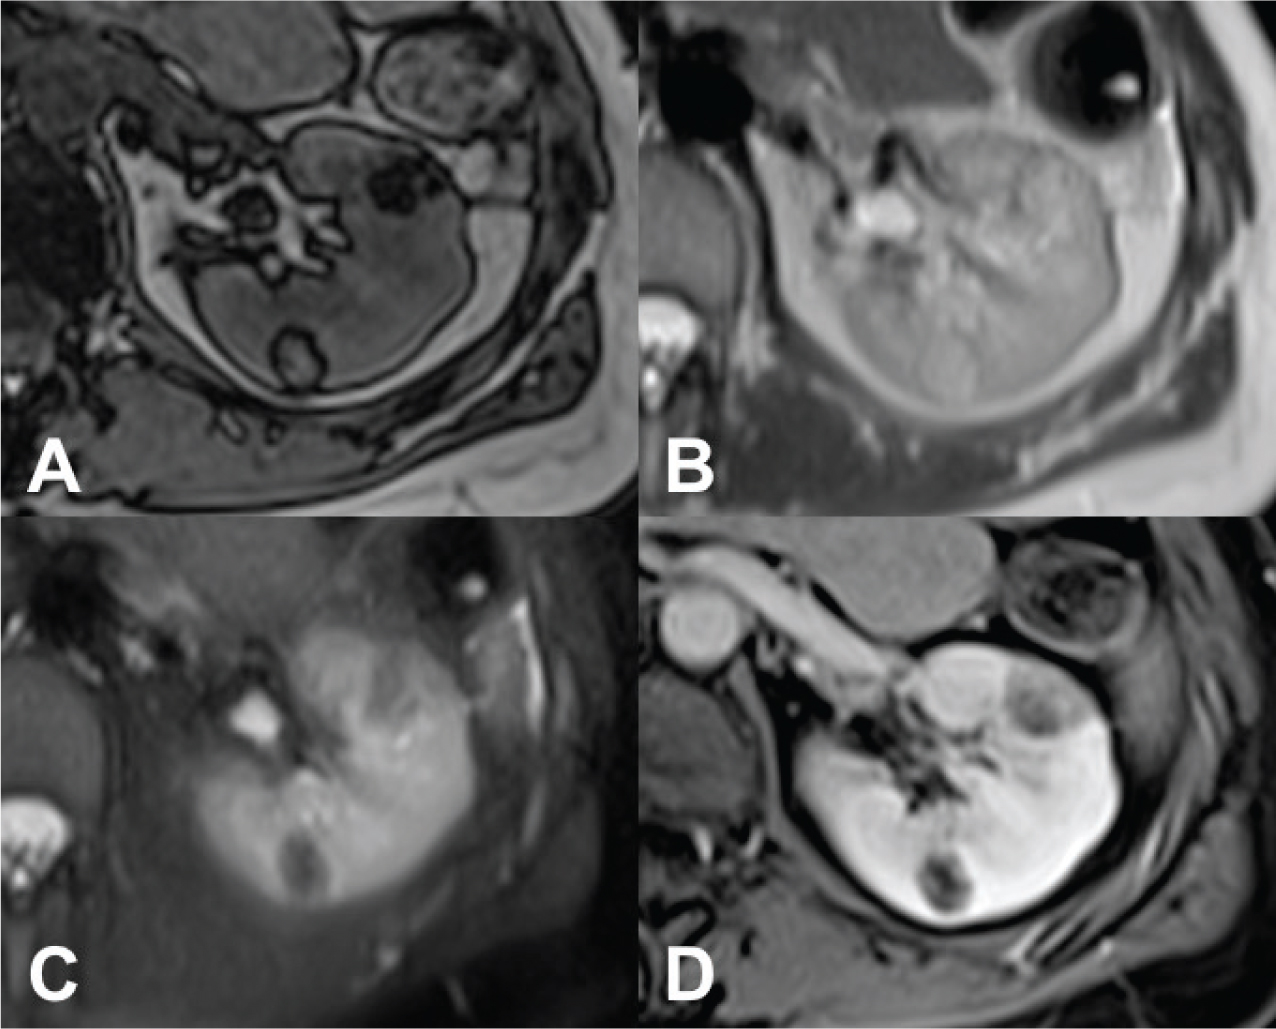

Tuberous sclerosis is largely the result of loss-of-function mutations of TSC1 (9q34) or TSC2 (16p13.3) genes. In addition to conditions such as mental retardation and seizures, TSC is associated with AMLs, LAM, pulmonary multifocal micronodular hyperplasia, subependymal giant cell tumors, cutaneous angiofibromas, and cardiac rabdomyomas (20). AMLs occur in 55–75% of patients with TS; AMLs in TS typically develop at a young age and are frequently multiple, almost always bilateral and larger in size, presenting as angiomyolipomatosis (Figure 1) (11, 21). Patients with TSC are more likely to show multiple, bilateral, and larger AMLs than AMLs in sporadic cases (22, 23). Most of the AMLs in TSC manifest as the classic type, while fat-poor AMLs are found in over one-third of these patients. Fat-poor AMLs in TSC tend to be larger than those of the sporadic form (24).

Fig 1

Figure 1. CT axial scan of the abdomen during venous phase of a 45-year-old woman with TS showing the presence of renal angiomyolipomatosis (A and B) and caliectasia at the level of the left upper calyceal group (A). Furthermore, a cystic lesion with solid peripheral tissue indissociable from the left inferior renal pole is evident (B). At the follow-up CT scan performed approximately 6 months later, the cystic lesion showed an increase of the solid component. Consequently, the patient underwent left nephrectomy and tumorectomy. Histological examination revealed the diagnosis of dedifferentiated liposarcoma.